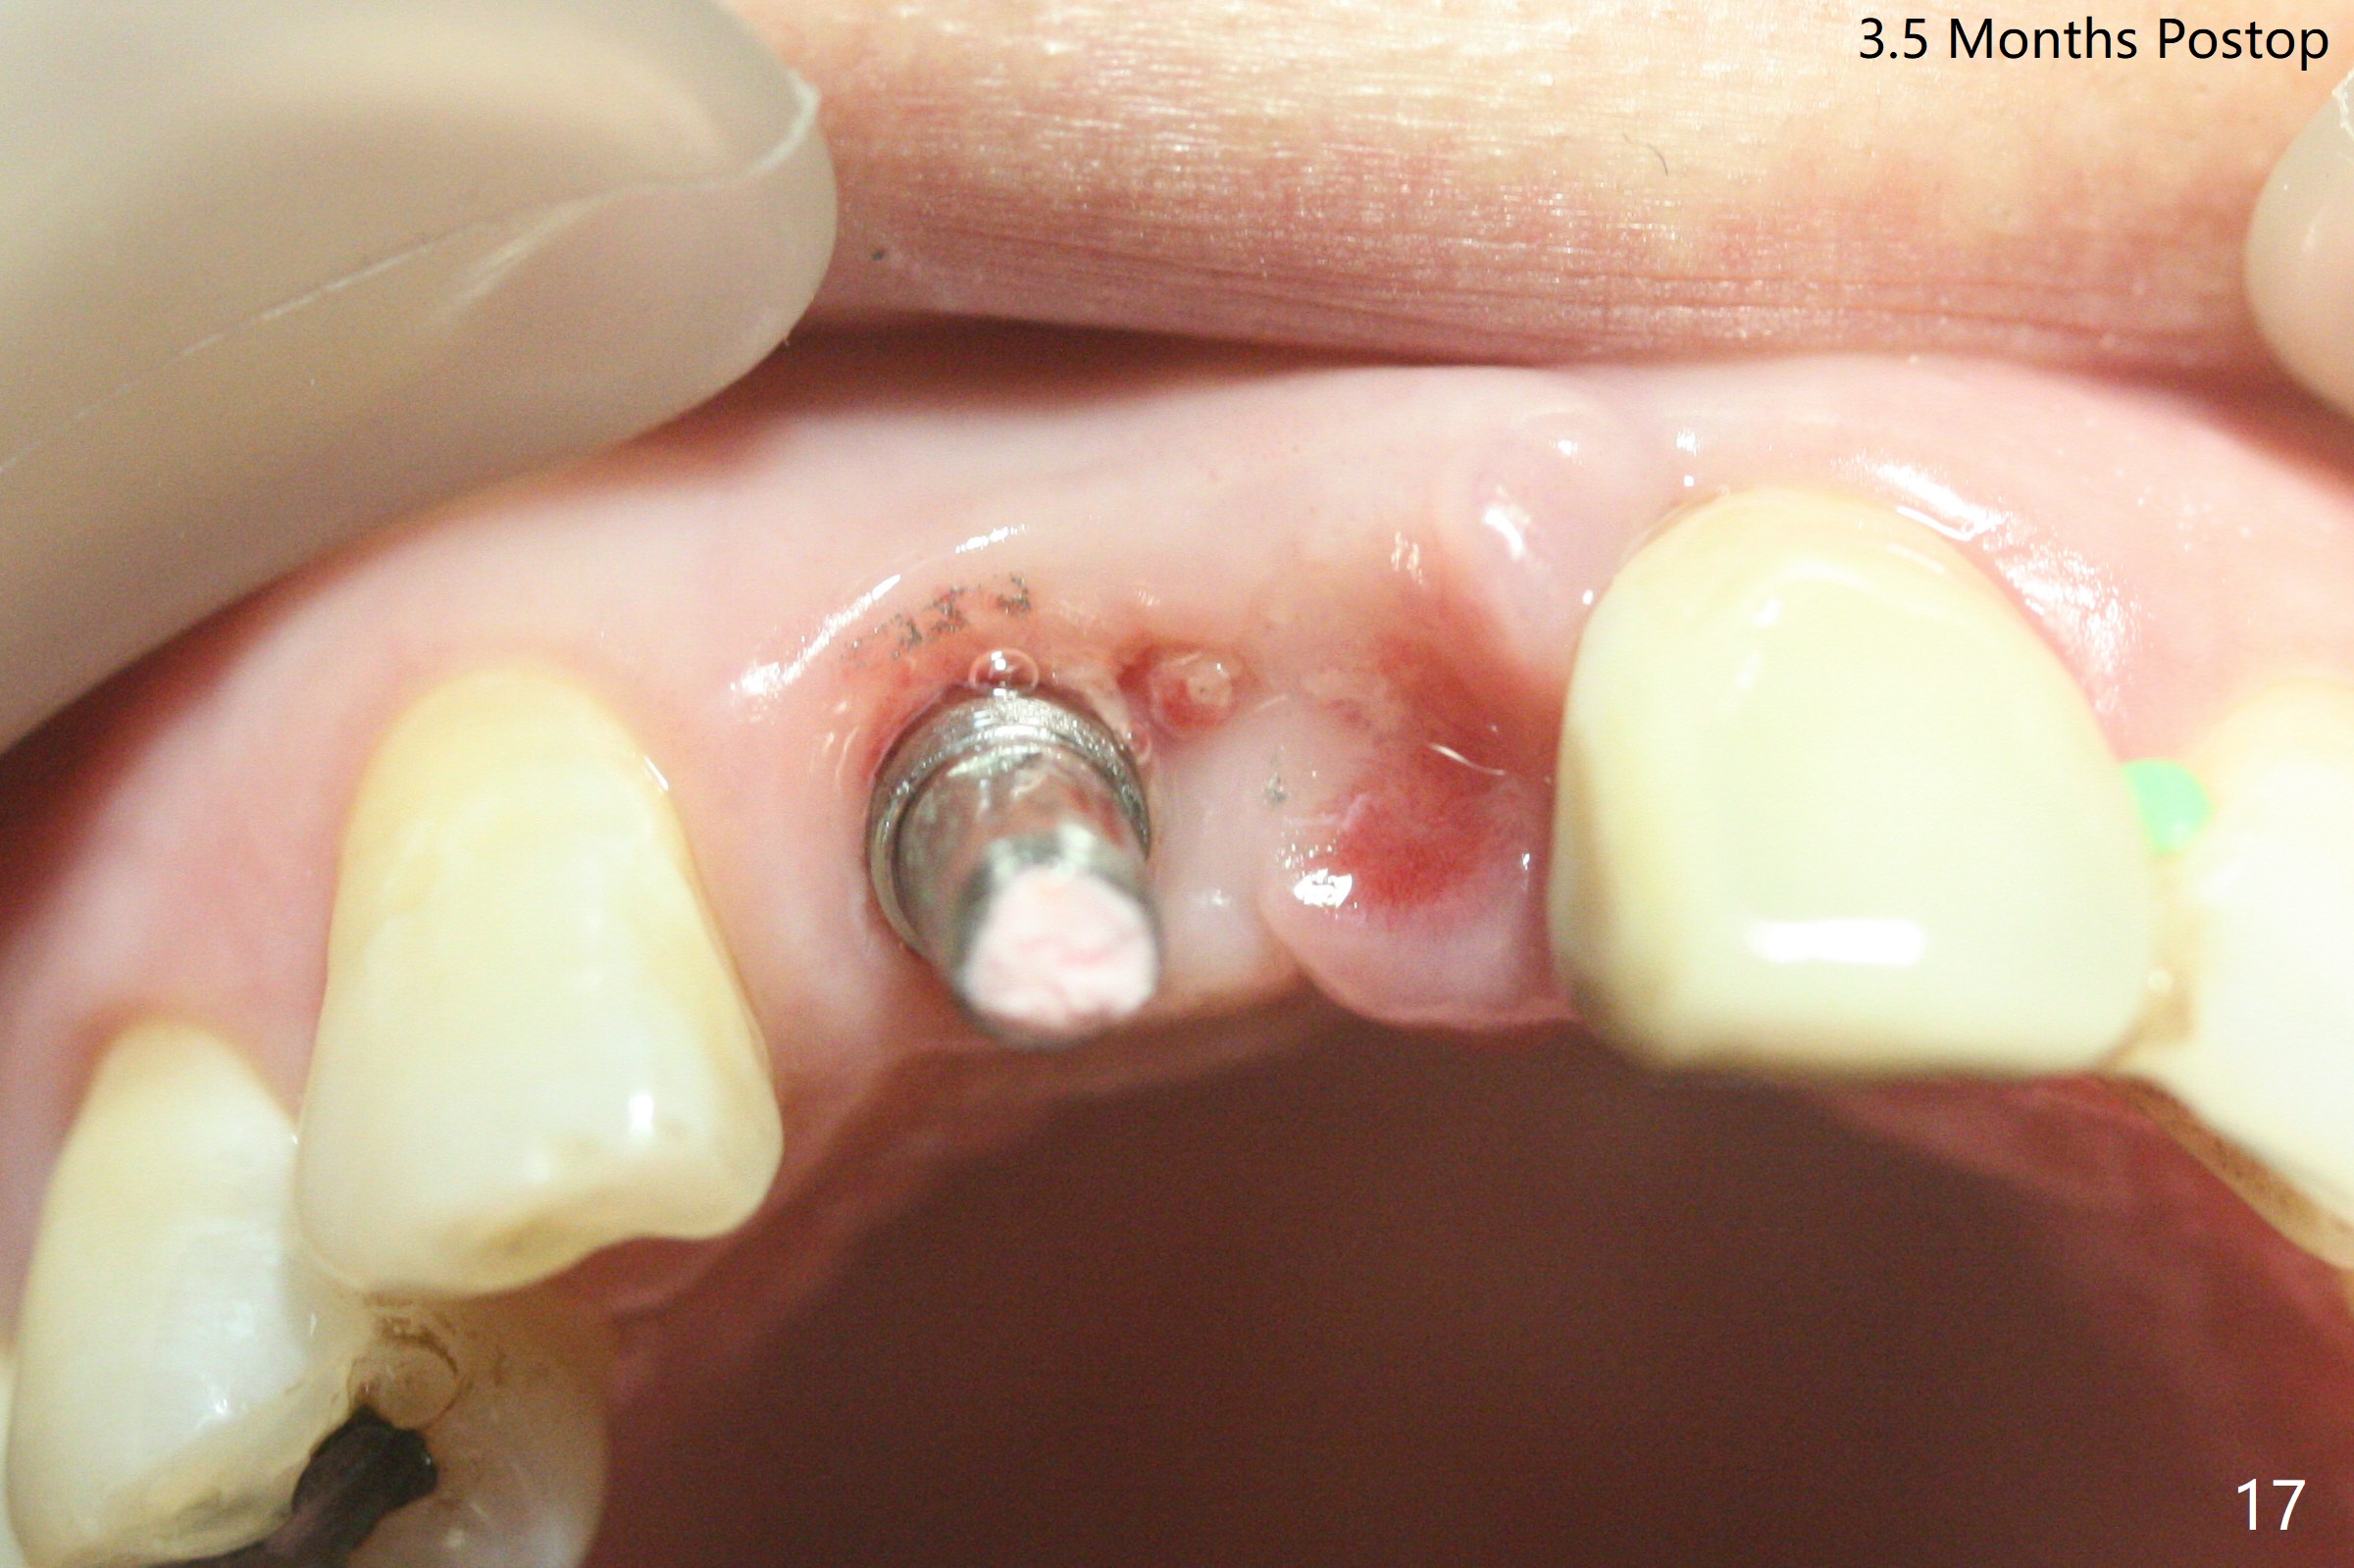

拆除部分桥发现:中,侧切牙牙龈红肿(图一),不利于切口和伤口愈合。不过还是在中切牙区切开,牙龈相当厚,有利于今后牙龈形成凹陷和乳头。坏消息是近远中距离太短,不利于植牙以及今后局部卫生维护,所以决定只在侧切牙种植(图二,三),完成钻洞后,颊侧根尖穿孔植骨,然后植入植体,即刻放置修复基台(图四 (*:牙龈乳头)),暴露基台牙龈缘,制作临时悬臂桥 (图五),两个中切牙牙冠长度差不多,插入临时桥时颊侧牙龈乳头基本形成(图六:*),缝合前颊侧,腭侧牙龈瓣下放置粘性骨块(图七,八:* )和PRF膜(图七:^)。最后使用牙周敷料。但愿术后牙龈炎症消失,形成良好牙龈乳头和pontic concavity。 其实由于口腔卫生习惯,术后十七天颊侧牙龈仍红肿(图九),而腭侧正常。如果口腔卫生改善而红肿依然存在,让实验室制作临时桥。术后一个月颊侧牙龈红肿好些(图十),好像骨粉丢失少许,可能与水枪使用有关。右上1牙冠显得太短(*)。也太肥大,因为右上1切缘太颊侧,与左上1对比(图十一:*)。由于颊侧牙龈(图十二:B)术中推向颊侧,与腭侧(P)牙龈之间放置大量粘性骨粉,术后一个月骨粉(<)形成牙龈,形成凹陷。颊侧萎缩不再明显了。右上1牙冠颈部多加些树脂,牙齿就显得长的多(图十三:箭头)。与侧切牙之间颈部故意留下间隙(*),让牙龈入位(空箭头),形成龈乳头。当右上1临时牙冠切缘(图十四:*)移到腭侧,外形改观不少。下次改善侧切牙唇侧。术后两个月三个星期牙龈红肿好像减轻,牙龈没有进入切牙间隙,干脆用树脂关闭(图十五:> <)。下次减少侧切牙切缘(^),适当增加中切牙长度(上提牙龈)。术后3.5个月植体好像整合,基台完全就位(图十六)。术后3.5个月Pontic凹陷形成,但是1,2之间龈乳头始终无法形成(图十七)。以后类似病例应该多种植一个。此例草率取模,可能需要临时粘固,观察植体近中颊侧所谓瘘道,必要刮治。由于比色不佳,需要实验室颜色更改,病人强化卫生,术后七个月,永久性牙冠粘固前,局部牙龈健康(图十八)。